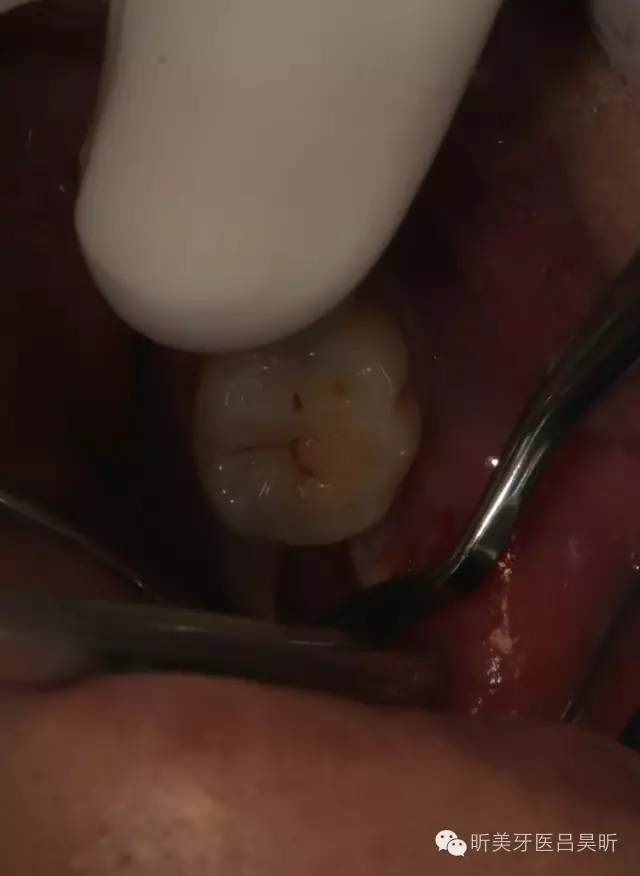

患者,男性,47缺失兩年。

術(shù)前口內(nèi)檢查,可見(jiàn)牙槽骨寬度良好,角化齦量適中